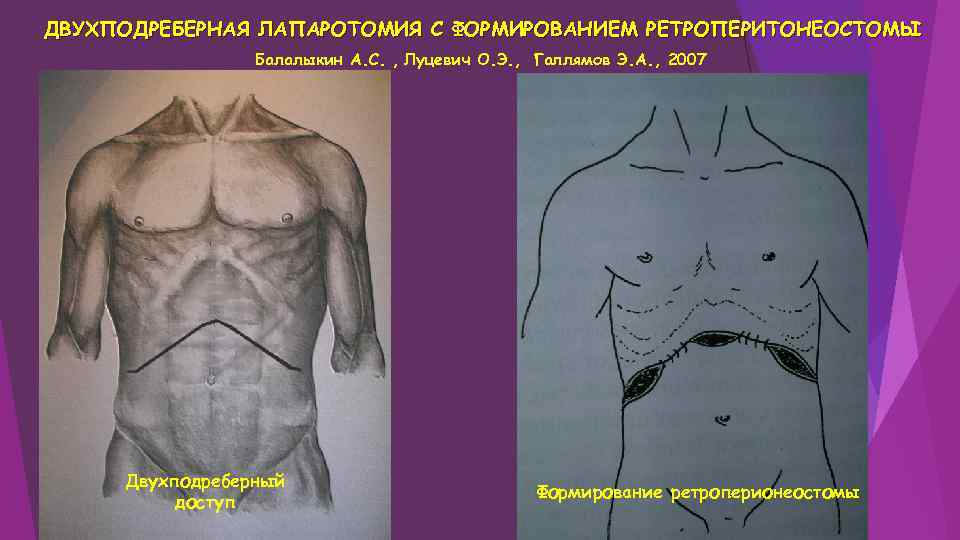

ДВУХПОДРЕБЕРНАЯ ЛАПАРОТОМИЯ С ФОРМИРОВАНИЕМ РЕТРОПЕРИТОНЕОСТОМЫ Балалыкин А. С. , Луцевич О. Э. , Галлямов Э. А. , 2007 Двухподреберный доступ Формирование ретроперионеостомы

ДВУХПОДРЕБЕРНАЯ ЛАПАРОТОМИЯ С ФОРМИРОВАНИЕМ РЕТРОПЕРИТОНЕОСТОМЫ Балалыкин А. С. , Луцевич О. Э. , Галлямов Э. А. , 2007 Двухподреберный доступ Формирование ретроперионеостомы